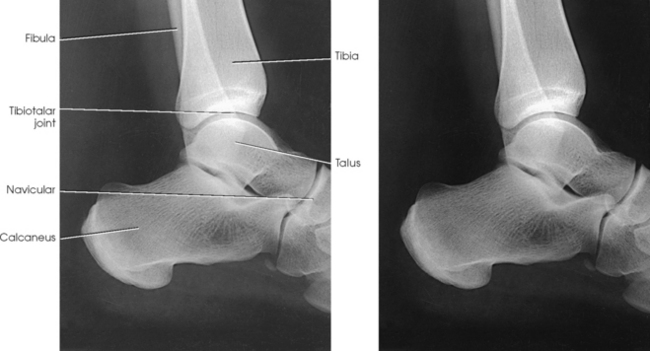

The joints of the lower limb are summarized in Table 6-1 and shown in Figs. 6-11 and 6-12. Beginning with the distalmost portion of the lower limb, the articulations are as follows.

Fig. 6-12 A and B, Joints of right foot. C, MRI sagittal plane of anterior foot. D, MRI sagittal plane of posterior foot and ankle. Joint spaces and articular surfaces are clearly shown.

The calcaneus supports the talus and articulates with it by an irregularly shaped, three-faceted joint surface, forming the subtalar joint. This joint is classified as a synovial gliding joint. Anteriorly, the calcaneus articulates with the cuboid at the calcaneocuboid joint. This joint is a synovial gliding joint. The talus rests on top of the calcaneus (see Fig. 6-12). It articulates with the navicular bone anteriorly, supports the tibia above, and articulates with the malleoli of the tibia and fibula at its sides.